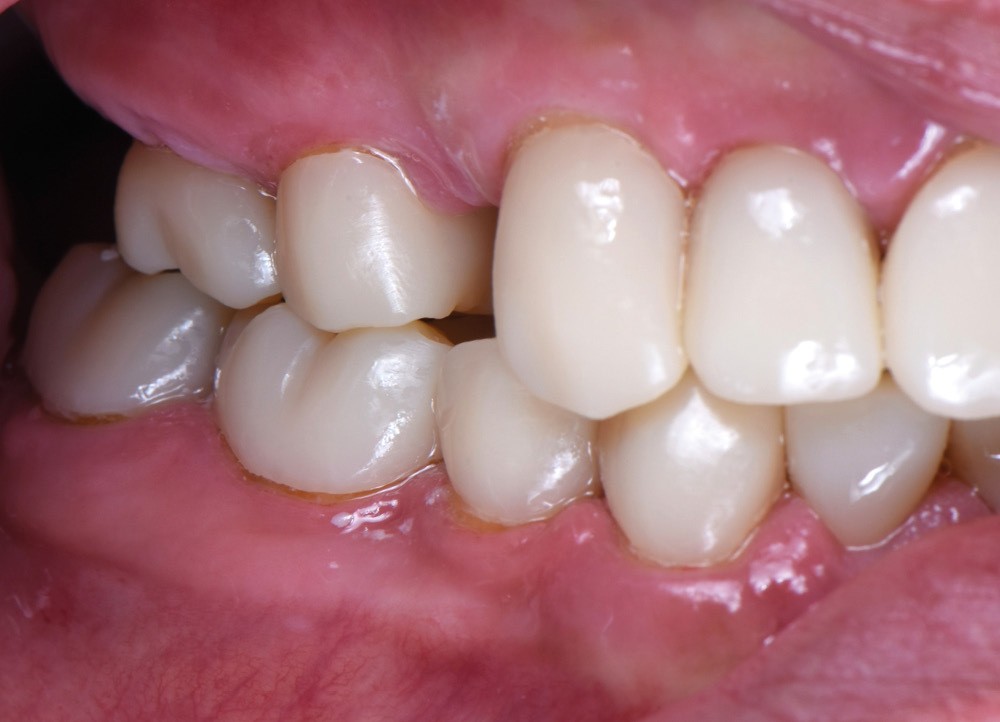

Au vu du contexte para-fonctionnel et de l’étendue de la perte tissulaire, des coiffes périphériques minimalement invasives ont été choisies afin de restaurer l’esthétique et la fonction. Actuellement, aucun consensus n’est fait sur le choix du matériau d’infrastructure à privilégier. Les matériaux hybrides usinables présentent des propriétés mécaniques, physiques et biologiques intéressantes en contexte d’usure sévère (e.g., module d’élasticité, résistance à la propagation de fêlures, facilité de réintervention). Une réhabilitation globale avec remontée de dimension verticale d’occlusion (DVO) par l’intermédiaire de coiffes composites renforcés en nano-céramiques est décrite.